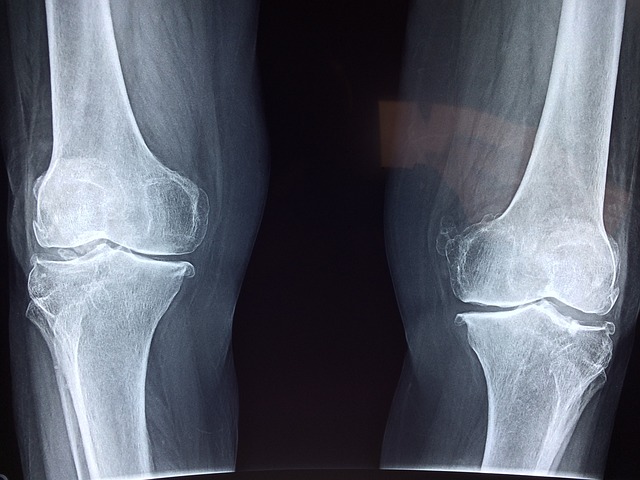

크론병과 관절염은 장과 관절 사이의 연결 또는 상호작용을 나타내는 장-관절 축 연결을 가지고 있습니다. 이 연결은 두 질환 간의 관련성을 보여주며, 크론병과 관절염이 동시에 발생하거나 한 질환이 다른 질환을 유발하는 경우가 많이 있습니다.

장-관절 축 연결은 면역 시스템과 염증 과정에서 중요한 역할을 합니다. 크론병은 장 내부의 염증과 관련된 만성 장질환으로 알려져 있습니다. 장 내부의 염증은 면역 시스템의 비정상적인 반응에 의해 시작되며, 이는 관절염의 발병과 진행에도 영향을 줄 수 있습니다. 따라서 크론병에서 발생하는 염증은 관절로 확산되어 관절염을 유발할 수 있습니다.

또한, 장-관절 축 연결은 염증 매개자나 화학 물질의 상호작용을 통해 크론병과 관절염 간의 연결을 형성할 수 있습니다. 장 내부의 염증 매개자가 혈류를 통해 관절로 이동하면 관절 내부에서도 염증이 발생할 수 있습니다. 이러한 염증 반응은 관절의 통증, 부종, 운동 제한 등을 초래할 수 있으며, 장-관절 축 연결을 통해 크론병과 관절염 간의 증상이 상호 영향을 줄 수 있습니다.